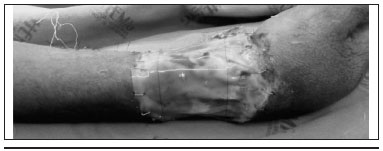

A lesao mais grave foi a circunferencial do punho direito, pois, além das extensas áreas de necrose muscular superficial e profunda, havia acometimento vascular e tendinoso (Figura 5). O paciente foi submetido a várias etapas de debridamento cirúrgico até a retirada completa do tecido necrosado.

Figura 5 - Lesao circunferencial em punho direito